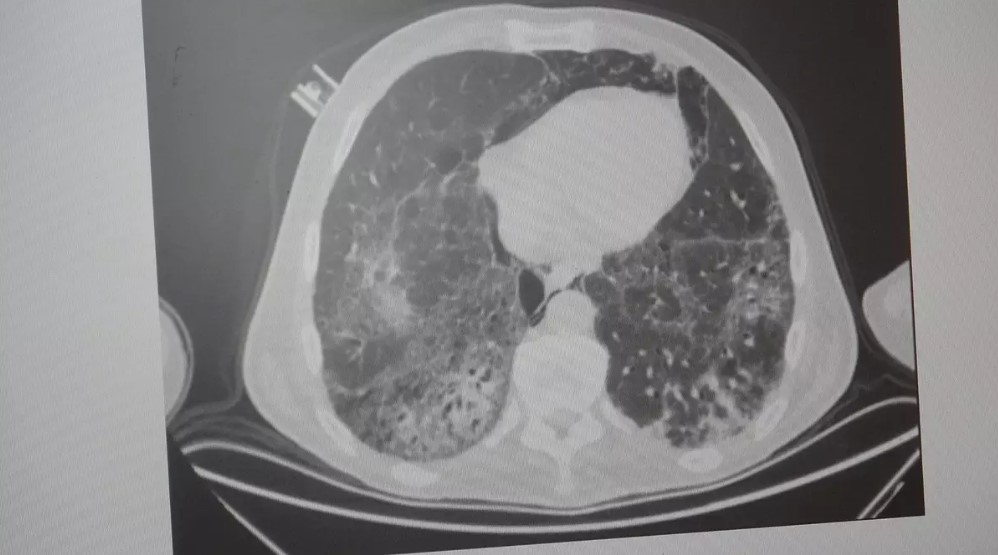

KOAH, akciğer dokusunun zamanla tahrip olmasıyla ortaya çıkıyor. Bu durum hastaları enfeksiyonlara karşı daha savunmasız hale getiriyor. Hastalık ilerledikçe nefes darlığı, kronik öksürük ve balgam artışı gibi belirtiler belirginleşiyor.

KOAH hastalarında zatürre geliştiğinde tablo daha da ağırlaşabiliyor. Özellikle 38,5 derece üzeri ateş, artan nefes darlığı, yoğun balgam, bilinç bulanıklığı gibi belirtiler ciddi enfeksiyonun habercisi olabiliyor.

Uzmanlara göre zatürre ve bronşit belirtileri benzer olsa da hayati farklar bulunuyor. Bronşit, hava yollarının iltihaplanmasıyla sınırlıyken; zatürre, akciğerin en uç noktalarındaki alveolleri etkiliyor.